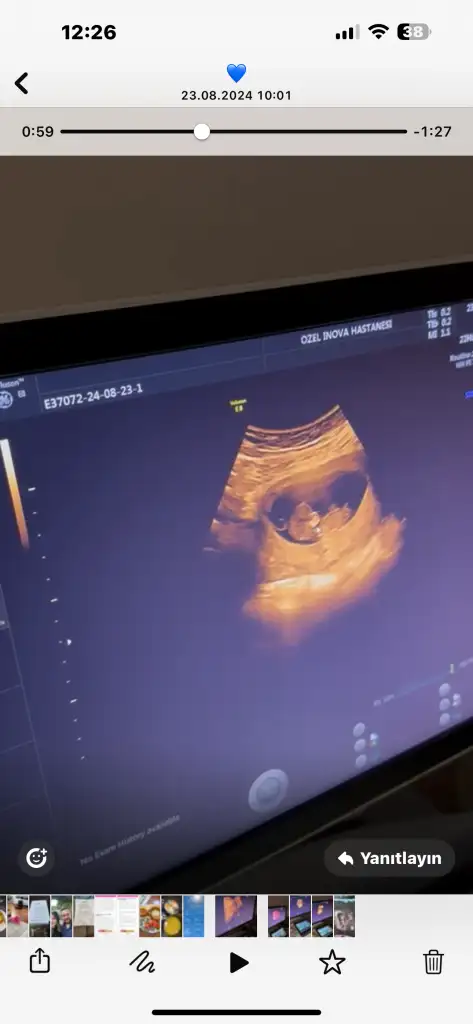

Maşallah mınnosuma benımKesinlikle yaptirmani öneririm, ikili tarama testinde burnu minik demişti Dr ama diğer her şeyi normal çok küçük ihtimal down olabilir dedi. Kendi doktorum da aynı şekilde amniyosentez yapabiliriz ya da fetal DNA dedi. O ara çok fazla ağladım çok fazla araştırma yaptim. Tüm organlar normal ama burnundan ötürü ihtimal var diye. Bir de hareketlerini de hissediyorsun nasıl kiyabilirsin. Sonraki aylar kontrole gittiğimde Dr yine bak burnu küçük hala devam ediyor o küçüklük dedi. Tam unuttum artık düşünmüyorum derken tekrar aklıma girdi o konu. Aldirmamakta kararlıydım sadece bilip kendimi hazırlamak istedim eşim de eğer öyle bir durum çıkarsa hamileliğin stresli geçer yaptirmayalim dedi. Çok şükür sağlıklı şekilde dünyaya geldi minnoşumbir daha çocuk yaparsam kesinlikle en başta test yaptırırım diyorum